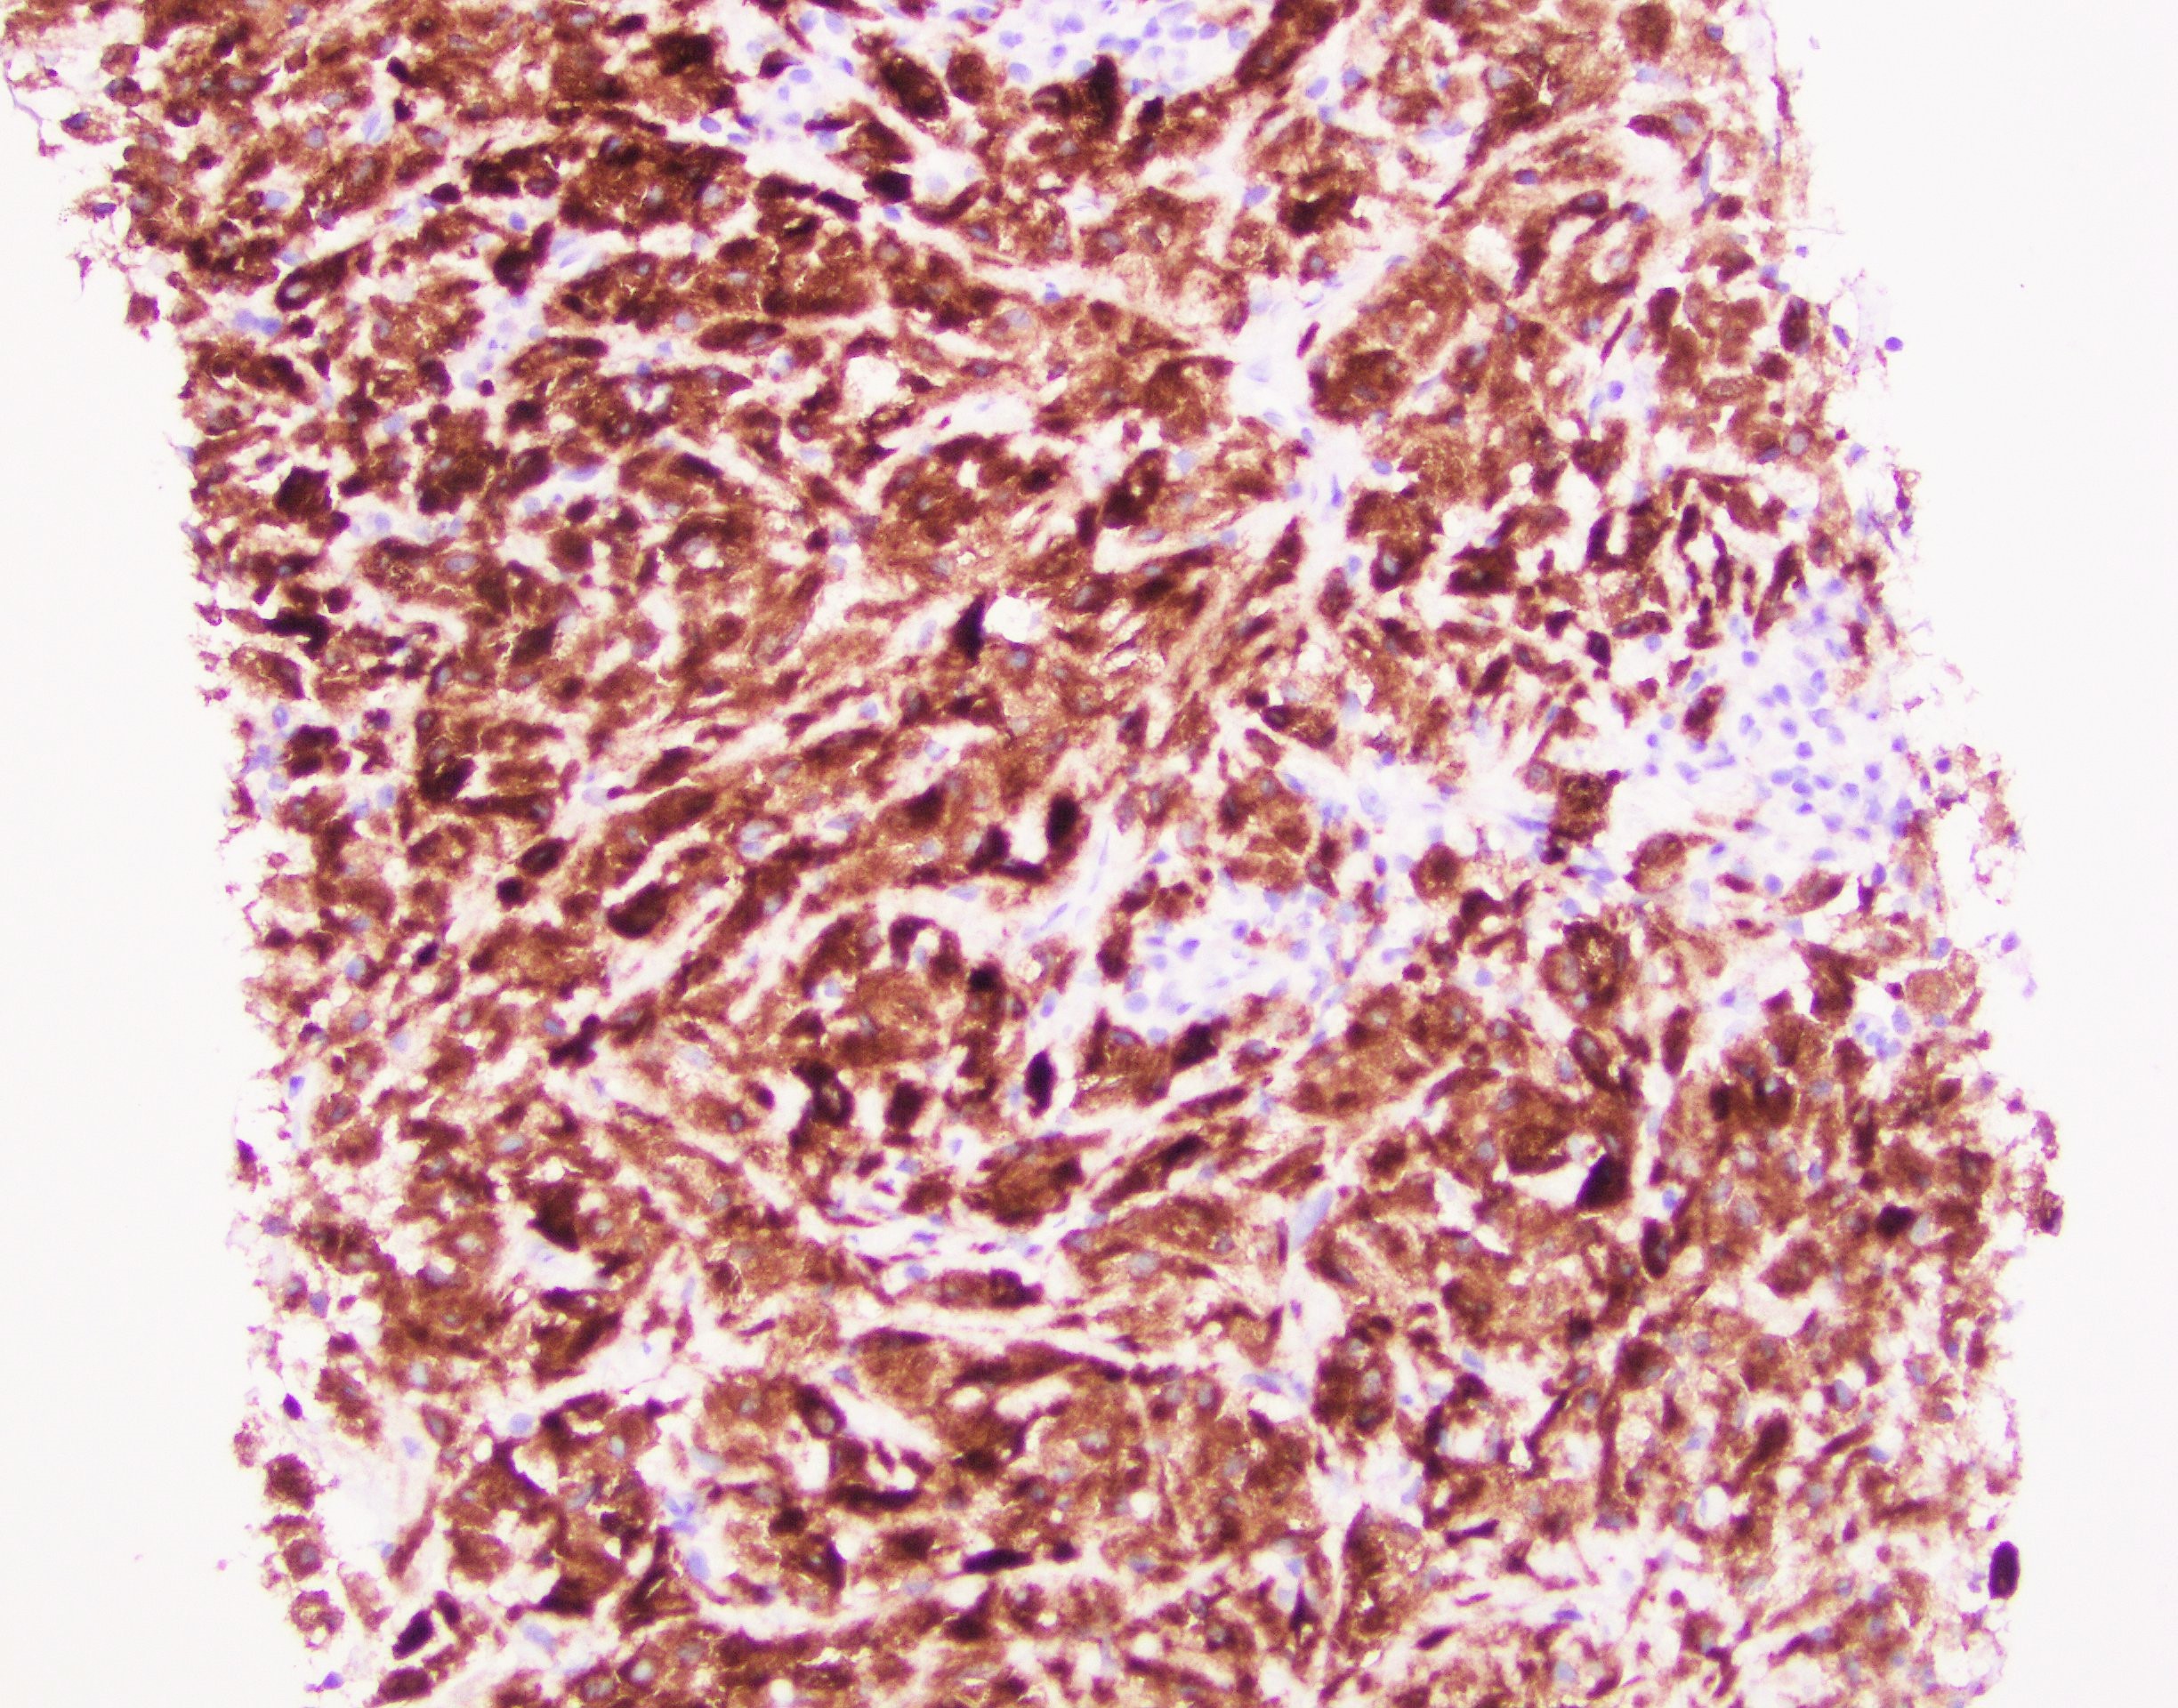

A 66-year-old female with right middle lobe lung lesion (A Sox10 immunostain was negative).

Explantation: H&E sections show a proliferation of histiocytic appearing cells containing brightly eosinophilic crystalloid material that is slightly refringent. In addition there are foci of plasma cells scattered throughout. Immunohistochemical stains for Keratin cocktail, PAX8, Sox10, CD68, CD163 and Kappa/Lambda cocktail were performed with appropriate controls. The cells of interest are strongly immunoreactive for CD68 and CD163 while negative for Keratin cocktail, Sox10 and PAX8. Kappa/Lambda cocktail shows a Kappa light chain restriction in the plasma cells present and the crystalloid material within the histiocytes is also immunoreactive for Kappa light chain.

The overall findings are most consistent with the so-called localized (pleuro) pulmonary crystal-storing histiocytosis a rare disorder that is often related to lymphoproliferative/plasma cell diseases and rarely occurs secondary to long-standing immune-mediated diseases (rheumatoid arthritis) or to chronic use of certain medications (clofazimine).